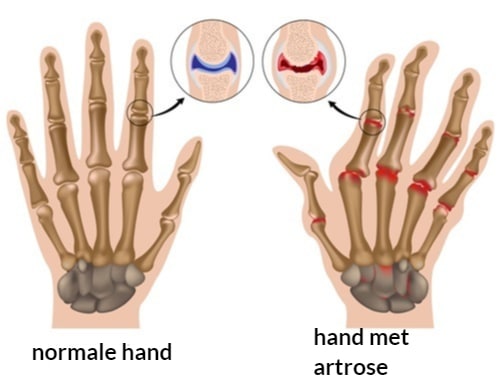

En juist die chronische ontstekingsprocessen en kraakbeenafbraak in je handen en vingers zorgen ervoor dat je klachten blijven terugkomen - omdat je lichaam in een constante staat van ontsteking en gewrichtsslijtage verkeert.

Artrose hand is meer dan alleen lokale pijn in hand - het is een duidelijk signaal dat je lichaam in een chronische ontstekingstoestand verkeert die je algehele gezondheid aantast.

Waar Komt Artrose Handen Vandaan?

Handartrose ontstaat niet zomaar.

Het is het resultaat van chronische ontstekingsprocessen en kraakbeenafbraak in je handen en vingers, meestal door een combinatie van factoren die elkaar versterken.